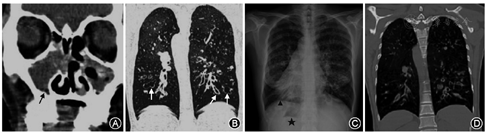

患者女,47岁,因反复鼻塞、流涕10年,加重2个月入院。患者10年前无明显诱因出现双侧鼻腔堵塞,无交替性,伴流脓涕,伴嗅觉减退,无头痛头晕,无面部麻木等。2个月前自感上述症状加重,伴咳嗽咳痰,于外院检查并诊断为卡塔格内综合征(KS)(图1A,图1B)。患者既往有"支气管扩张、慢性阻塞性肺疾病"病史多年,长期使用噻托溴铵、家庭氧疗(包括无创呼吸机)等治疗。否认家族遗传病史,祖父母为近亲结婚。查体:生命体征平稳,双肺呼吸音稍粗,可闻及少量干湿啰音,心尖搏动位于右锁骨中线第5肋间,在胸部右侧可闻及心音。实验室检查无明显异常。心电图示右位心,窦性心律,多发室早。胸片显示双侧支气管扩张合并感染可能性大(图1C)。肺功能检查:极重度阻塞性肺通气功能障碍,中重度限制性肺通气功能障碍。鼻内镜检查:双侧中鼻道可见息肉样新生物,并可见脓性分泌物。暂予以地塞米松静滴、倍氯米松雾化、头孢孟多抗感染治疗,6 d后全麻下行鼻内镜下鼻窦开放+鼻息肉切除术。麻醉医师术前访视,患者体重55 kg,心功能Ⅲ级,咳嗽较前好转,双肺未闻及明显湿啰音,判断肺部病情稳定。

患者入手术室后生命体征平稳,血氧饱和度(SpO2)93%,血气分析:动脉血二氧化碳分压(PaCO2)42.0 mmHg(1 mmHg=0.133 kPa),动脉血氧分压(PaO2)61.8 mmHg,K+3.3 mmol/L。予以静脉补钾1 g,并静脉注射0.5 mg戊乙奎醚。麻醉诱导:咪达唑仑2 mg,舒芬太尼10 μg,丙泊酚80 mg,顺式阿曲库铵10 mg,瑞芬太尼75 μg。插管后采用压力控制模式控制呼吸,气道峰压(PEAK)25 cmH2O(1 cmH2O=0.098 kPa),潮气量(Vt)230 ml。听诊哮鸣音,予以沙丁胺醇4揿,呼吸道阻力下降。改呼吸参数为PEAK 30 cmH2O,呼气末正压(PEEP)6 cmH2O,Vt 330~360 ml,呼吸频率(f)14次/min,吸呼比1/2,氧浓度(FiO2)60%。血气分析:PaCO2 49.7 mmHg,PaO2 120 mmHg。术中以2%七氟醚吸入,辅助少剂量丙泊酚、瑞芬太尼持续泵入维持麻醉。半小时后,呼吸末二氧化碳分压(PETCO2)突然上升至75 mmHg,潮气量骤降,心率、血压有上升趋势,双肺痰鸣音明显。FiO2改为100%,并予以吸痰,可吸出中量淡黄色黏液痰,喷入沙丁胺醇。视潮气量情况调整压力参数,保证呼吸平台压<30 cmH2O(PEAK 31~35 cmH2O),PETCO2波动在58 mmHg上下,心率约100次/min,血压约110/80 mmHg。期间血气分析:PaCO2 60 mmHg,PaO2 300 mmHg。手术结束,支气管镜下可见大量黄色脓痰,并予以肾上腺素盐水盥洗。待患者自主呼吸恢复,Vt约320 ml,f 15次/min,血气分析(FiO2 30%):PaCO2 65.4 mmHg,PaO2 89 mmHg。带气管导管转入ICU,查体:心率120次/min,血压98/56 mmHg,f 33次/min,双肺呼吸音粗,可闻及大量痰鸣音及湿啰音。血气分析(FiO2 60%):PaCO2 98.2 mmHg,PaO2 154 mmHg;血常规:白细胞19.02×109/L,中性粒细胞百分比94.1%。予以哌拉西林舒巴坦抗感染、呼吸机辅助呼吸、化痰、镇静、镇痛等治疗。并行支气管镜检查:右下叶、左上叶、左下叶可见大量白色脓性分泌物,抽吸不尽。术后2 d,患者体温38.3 ℃,白细胞值明显增高,胸部CT示双侧支气管扩张合并感染(图1D),血气分析提示患者顽固性低钾,并诱发频发室性早搏。继续予以抗感染、化痰、补钾、支气管镜检查、体位引流等治疗,鼓励患者主动咳痰。痰培养示:铜绿假单胞菌。术后4 d,患者气道内痰液仍多,但神志清,肌力可,咳嗽锻炼可。为避免导管源性感染,予以拔管、无创辅助通气、间断端坐位等处理。3 d后,患者在家庭呼吸机辅助下生命体征平稳,予以转回专科病房治疗。